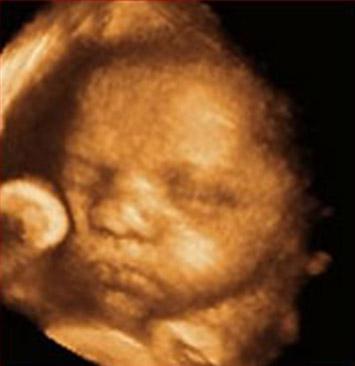

The number of children suffering severe disabilities after treatment for a deadly condition affecting just over 10% of all identical twin pregnancies could be significantly cut after University of Birmingham, UK, researchers developed a laser-based treatment, in collaboration with other experts in Europe.

A team led by Birmingham's Prof. Mark Kilby carried out a study into a modified laser treatment to reduce the number of babies born with a disability arising from Twin-Twin Transfusion Syndrome (TTTS). The study, published this week in medical journal The Lancet, reveals that the new technique, known as the "Solomon method", can reduce both the recurrence of TTTS and associated disabilities.

Although the number of babies that died was similar for both treatments, the Solomon technique led to fewer babies being born with severe complications that could lead to disability; 8% rather than 13% for the conventional treatment. The usual treatment for TTTS is to insert a thin needle, called a fetoscope, through the mother’s abdomen, visualising the placental blood vessels and, with a laser, selectively coagulating the blood vessels to stop the flow of blood between the two babies.

The Solomon technique involves lasering the entire placental vascular equator; that is, lasering the blood vessels but then also a circuit around the placenta in a bid to try to sever any tiny blood vessels which are not visible but may cause problems after treatment.